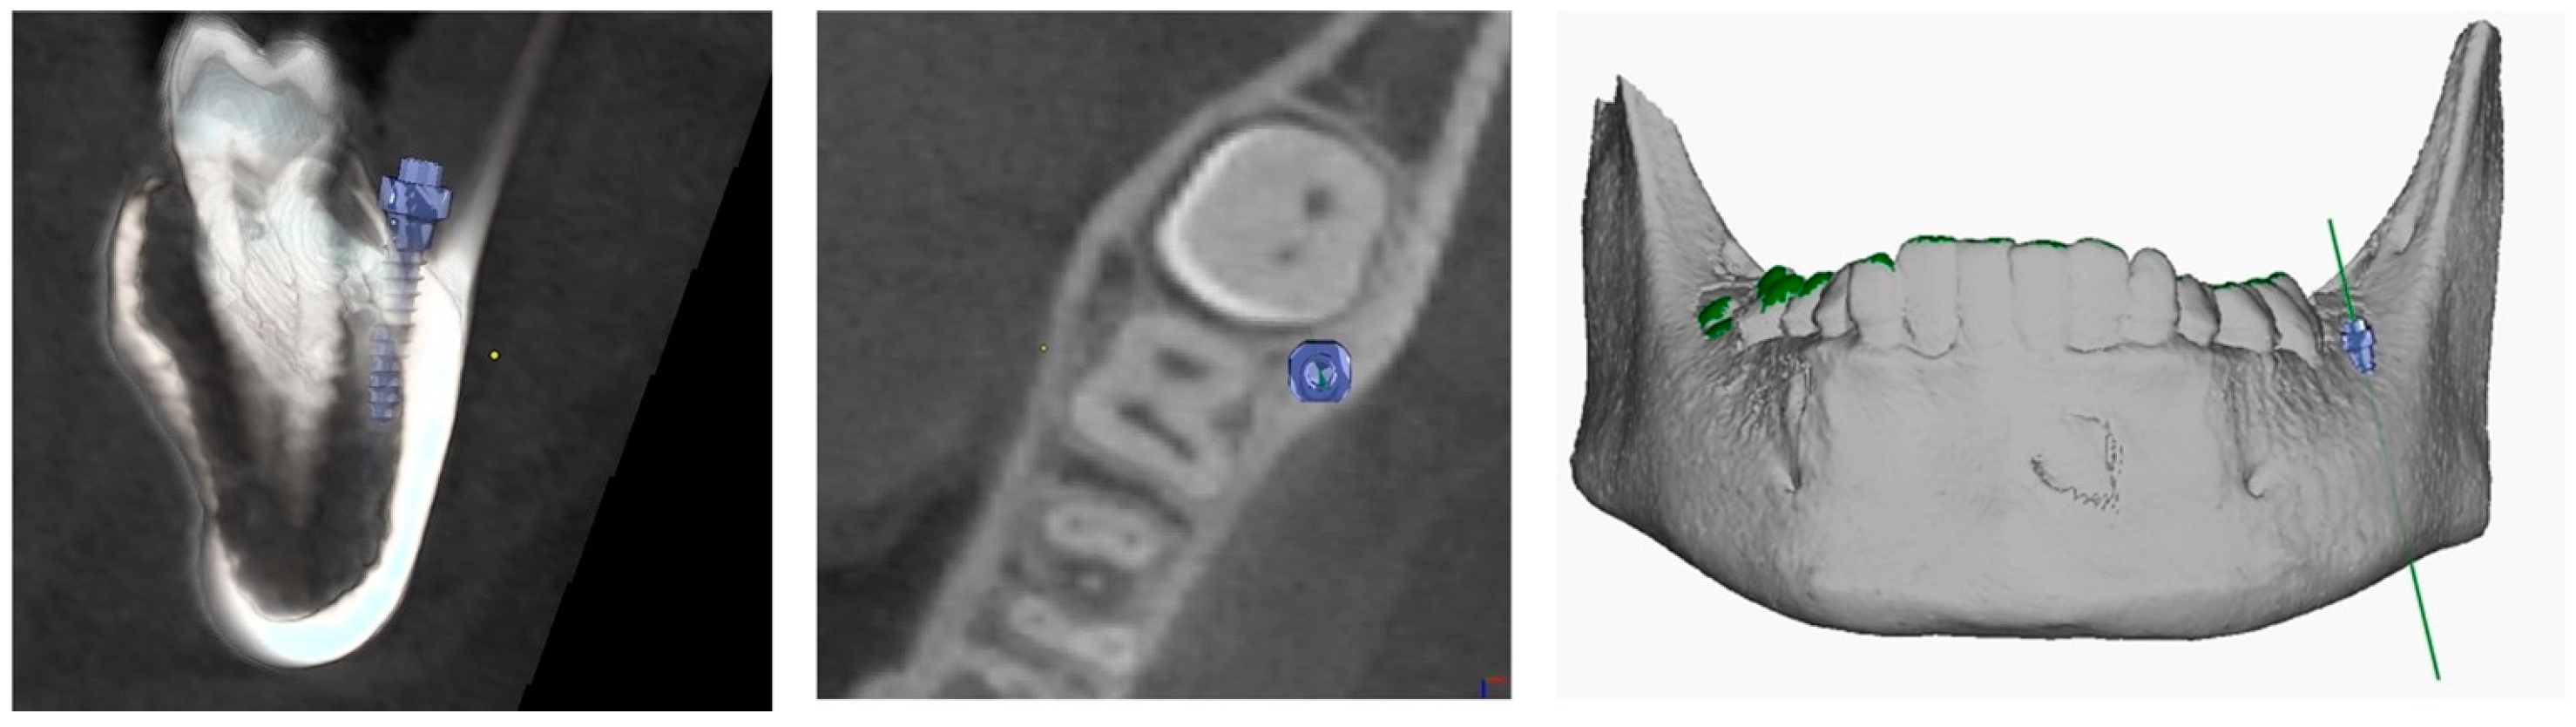

The procedure and potential risks associated with canine disimpaction, with particular emphasis on the risk of root resorption to adjacent elements, were fully explained to the subject and parents and signed informed consent for the publication of images and data was obtained. The disimpaction treatment consisted of a surgical phase of exposure of the impacted canine, with the possible removal of eruptive obstructions, and an orthodontic traction phase performed with a custom-made skeletal and dental anchorage device. The miniscrew insertion sites were planned on 3D images generated by merging CBCT and digital dental model images. The TADmatch 3D module of the Onyxceph3™ software (Image Instruments, Chemnitz, Germany) was used for the computer-guided planning of screw insertion using a surgical guide (Figure 5). A CAD/CAM digital workflow was performed to design the surgical guide and the skeletal anchoring disimpaction device using the Ortho Apps 3D module of the Onyxceph3™ software 3.2.180 Build 492–K2 (Image Instruments, Chemnitz, Germany) (Figure 6). The surgical guides were fabricated using TruPrint 1000 (TRUMPF Homberger S.r.l, Buccinasco, Italy) and the disimpaction device by laser melting technology with cobalt chrome metal powder (Stratasys OrhoDesktop; Stratasys, Rehovot, Israel) (Figure 7).

The length and diameter of the self-drilling titanium miniscrews used (BENEfit, PSM medical solutions, Tuttlingen, Germany) were predetermined during the planning phase based on bone anatomy (length: 13 mm; diameter: 2.3 mm). The miniscrew was inserted in the buccal shelf of the mandible, at the level of the mandibular first molar, on the left side; the appliance extended buccally from the miniscrew until the crown of the deciduous canine with a terminal hook and progressively distal holes for the insertion of orthodontic traction. Given the distance of the miniscrew from the disimpaction site, the device was designed to be very rigid with steel alloy with the rest cemented to the dental elements, which also had the function of preventing the device from rotating given that miniscrews are not equipped with effective anti-rotation devices.

Figure 5. Planning of miniscrew insertion on CBCT (Cone Beam Computed Tomography) from different views.